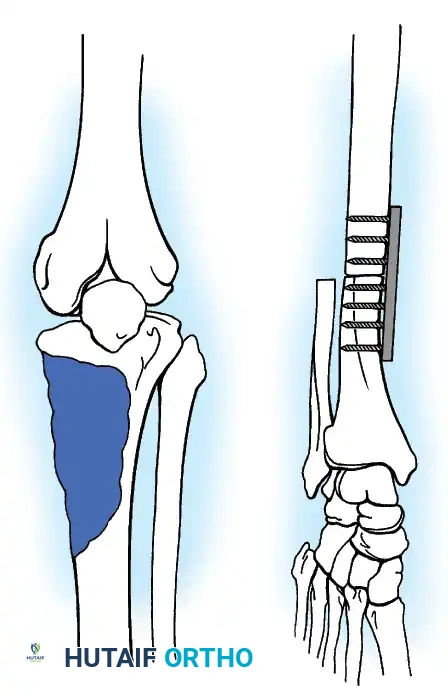

Clinical Pearl: When utilizing an Allograft-Prosthetic Composite (APC), step-cut osteotomies at the host-allograft junction combined with rigid plate fixation significantly increase rotational stability and union rates compared to transverse osteotomies.

Advanced Reconstructive Modalities and Distal Extensions

While proximal humeral resections dominate shoulder oncology, tumors extending into the humeral diaphysis or distal humerus require equally complex limb salvage strategies. Total humeral replacement or distal humeral megaprostheses are viable options when the radial nerve can be preserved or grafted.

Distal Humerus and Elbow Reconstruction

When tumors involve the distal humerus, resection often requires sacrifice of the collateral ligaments and the articular surface of the elbow. Reconstruction is typically achieved using a linked, semi-constrained total elbow arthroplasty designed for oncologic defects.